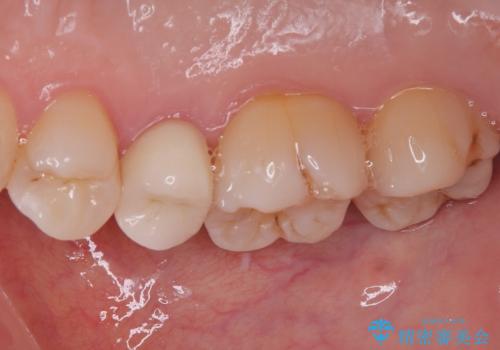

オールセラミッククラウンによる奥歯のむし歯治療

やはりむし歯は大きく、一部歯髄を切除することとなりましたが、その後は良好な経過をたどっています。